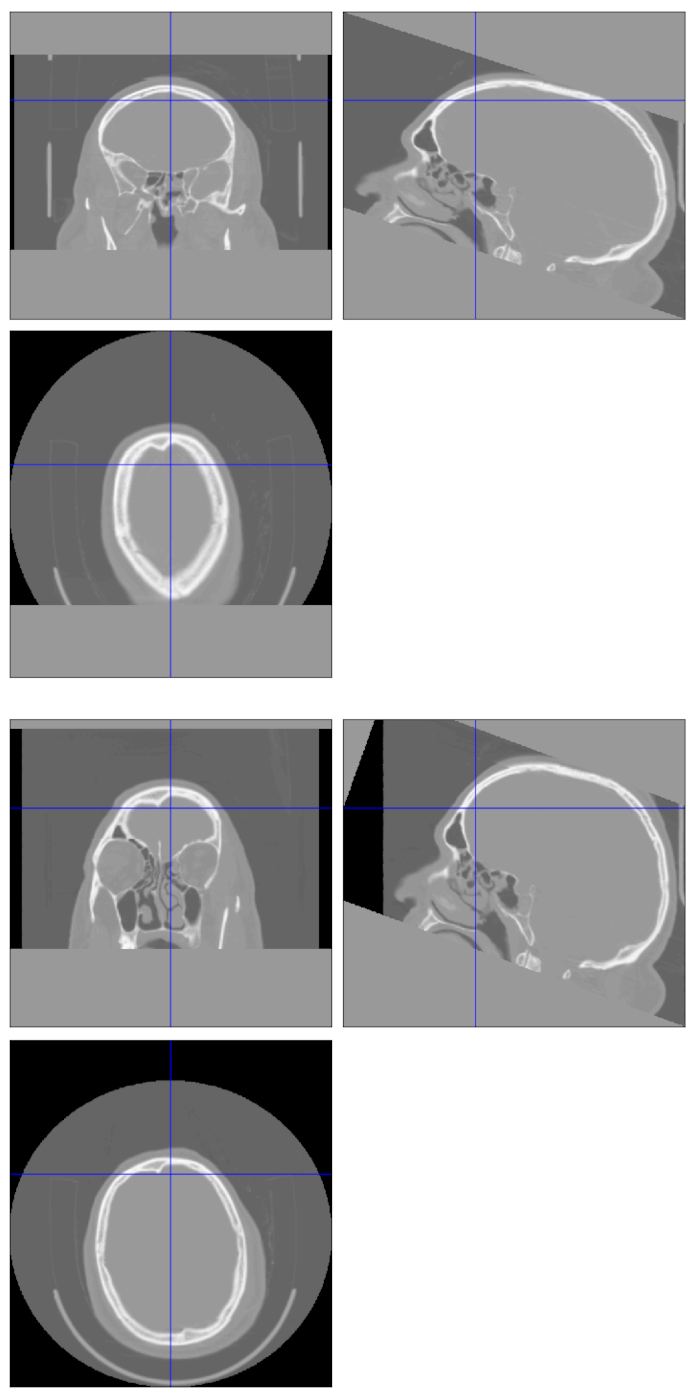

I have tried to reproduce Chris' results here. When I compare the images with and without tilt correction using SPM Check Reg, the shear appears to be correctly applied to both, but the uncorrected one looks longer anterior to posterior. The screenshot is from the open CQ500 dataset, but my concern is with my local hospital data, which has a similar effect.

Uncorrected Corrected

Dimensions 512x512x256 512x645x256

Voxel size -0.45, 0.50, 0.56 -0.45 0.45 0.62